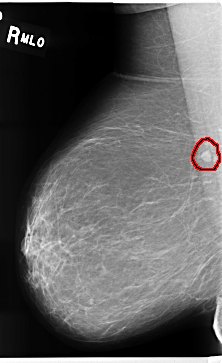

C_0210_1.RIGHT_MLO

FILE: C_0210_1.RIGHT_MLO.OVERLAY

TOTAL_ABNORMALITIES 1

ABNORMALITY 1

LESION_TYPE MASS SHAPE OVAL MARGINS CIRCUMSCRIBED

ASSESSMENT 3

SUBTLETY 5

PATHOLOGY BENIGN

TOTAL_OUTLINES 1

BOUNDARY